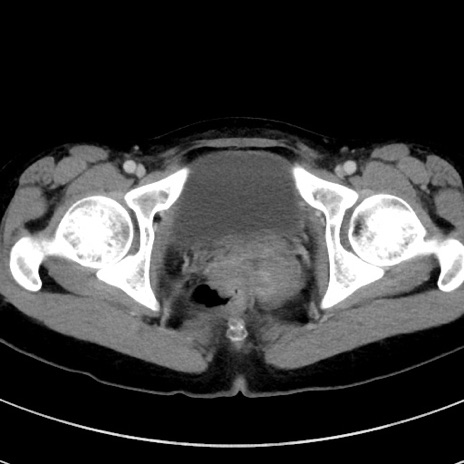

症例17(横断像)

【症例】20歳代女性

【主訴】嘔吐、下腹部痛

【現病歴】昨日夕食後に嘔吐し下腹部痛が出現。本日になっても嘔吐持続し改善しないため来院。

【身体所見】意識清明、BT 37.2℃、BP 108/67mmHg、腹部:平坦、やや硬、下腹部正中から右にかけて圧痛あり、反跳痛軽度あり、tapping pain(+)。

【データ】WBC 13600、CRP 14.94